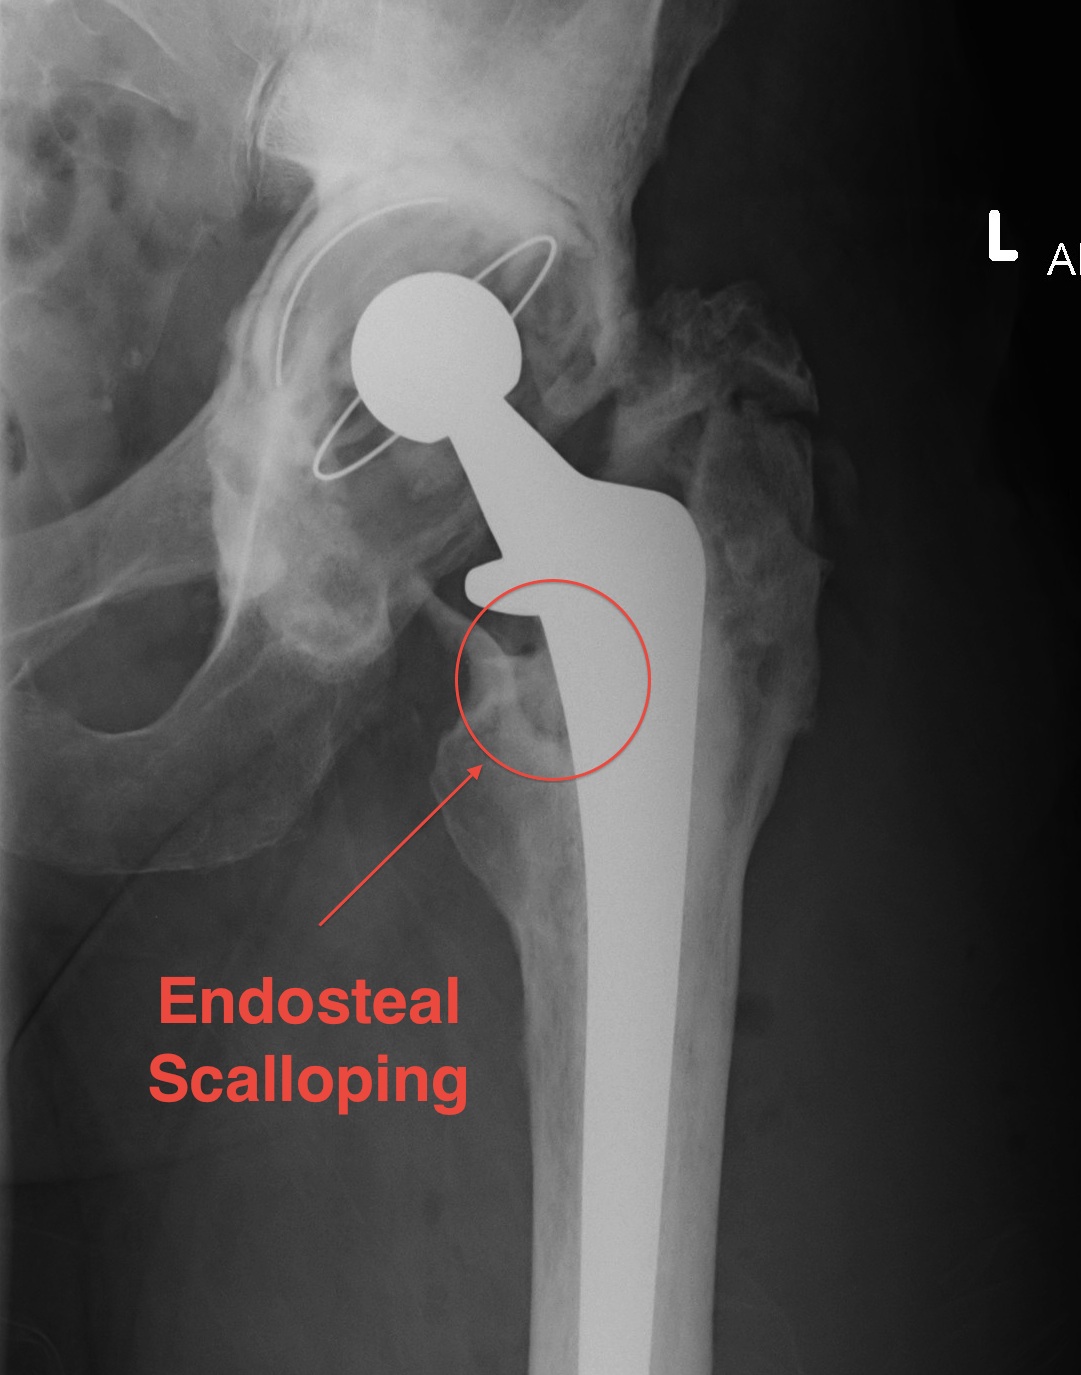

X-ray

1. Progressive radiolucent lines / rapid lysis

2. Focal osteolysis with endosteal scalloping

3. Periosteal new bone

Femoral stem lysis Acetabular lysis